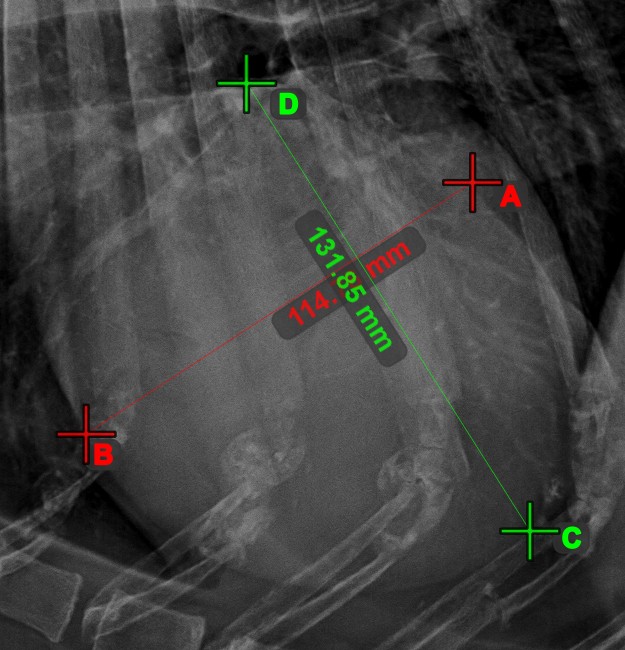

Measurement Point¶

Measurement Point

tool. Each point is assigned with a letter for better identification.Select/Move Item

tool. Select the point by using the assigned mouse button of the tool, and then move it freely anywhere on the image.